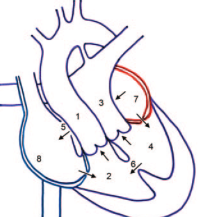

Tetralogie de Fallot

- Horizontalisation du Coeur (du à l’hypertrophie pulm)

- Signe du Coeur en Sabot (apex surelevé)

- Non visibilité du tronc pulmonaire

- Tetralogie:

- CIV

- Aorte à cheval

- Sténose et hypoplasie de l’infundibulum pulmonaire

- Hypertrophie du VD

- Si CIA associée = Pentalogie de fallot

- 1/4 des Fallots ont un arc aortique droit sans cardiomégalie ni vasculature pulmonaire augmentée (contrairement au TAC)